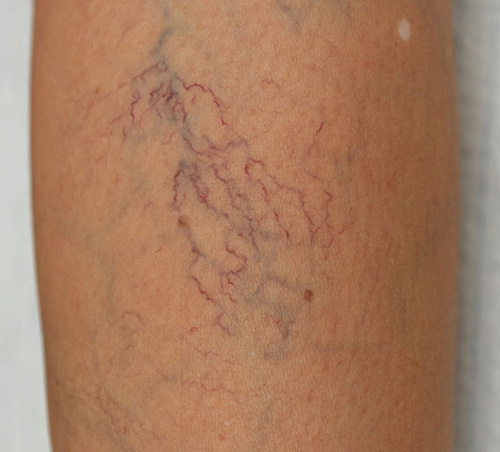

静脉曲张早期表现为腿部皮肤冒出红色或蓝色、像是蜘蛛网、蚯蚓的扭曲血管,或者像树瘤般的硬块结节,静脉异常的扩大肿胀和曲张。